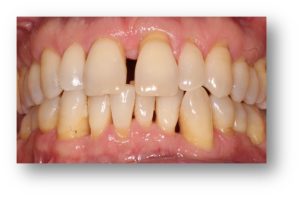

Before and after Periodontal Therapy

| Untreated severe gum disease | Gum disease treated and stabilised by Dr Halai |